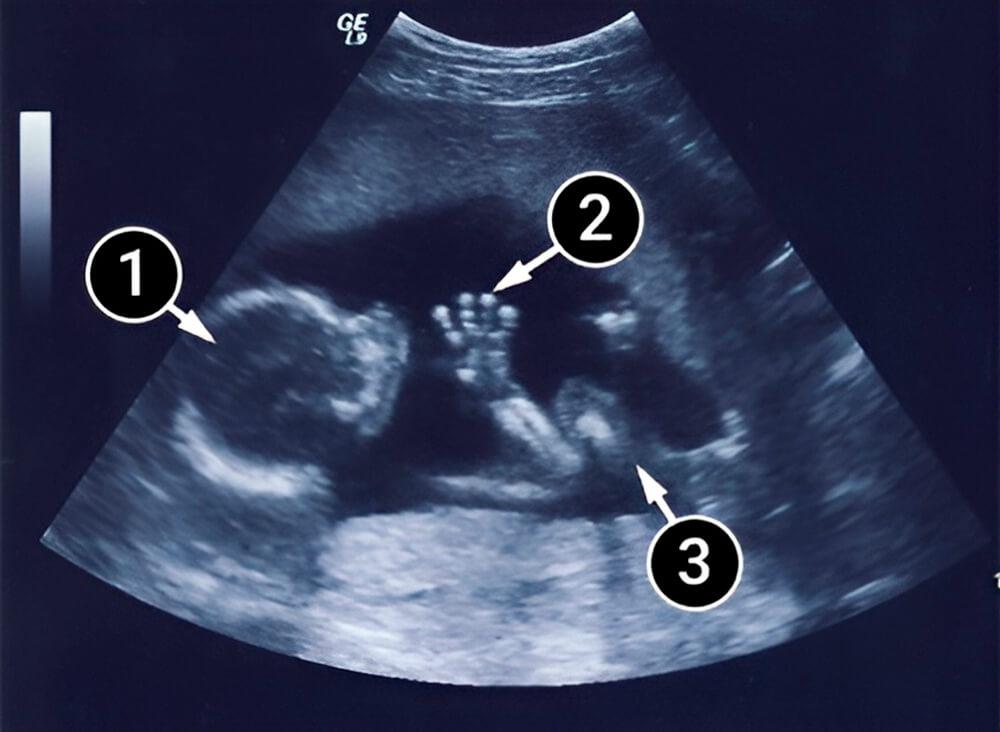

¿Qué se puede ver en la ecografía/ultrasonido?

Esta imagen muestra al bebé acostado de espaldas, mirando un poco hacia ti. Su perfil es bastante visible, con frente, nariz y mentón. Su mano derecha casi parece estar realizando un gesto acogedor, con la palma, la muñeca y los cinco dedos visibles.

Sus pies descansan contra la pared uterina. La rodilla derecha es visible, mientras que la izquierda está muy oscurecida.